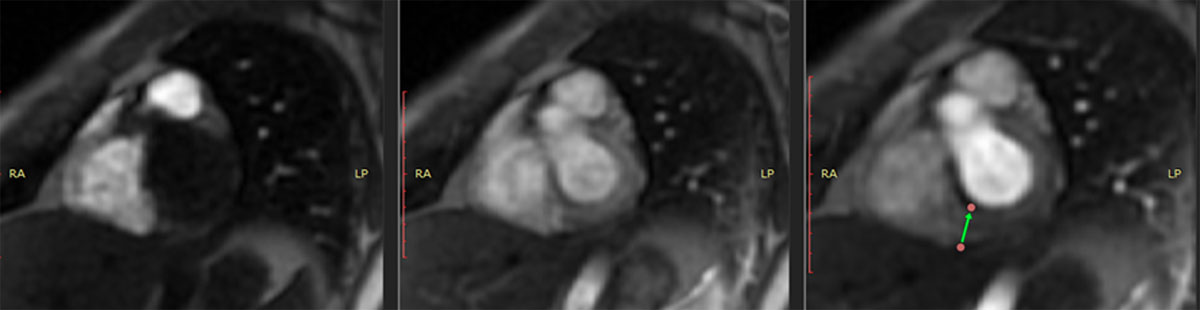

Cardiac magnetic resonance imaging (MRI) with gadolinium revealed normal-sized cardiac chambers, preserved right ventricular function, and a LVEF of 52% (lower than the normal range) in a context of mild hypokinesia of the inferior wall of the left ventricle (basal and medial segments) (Figure 3).

Figure 3

Cardiac MRI showing hyperemia in the basal portion.